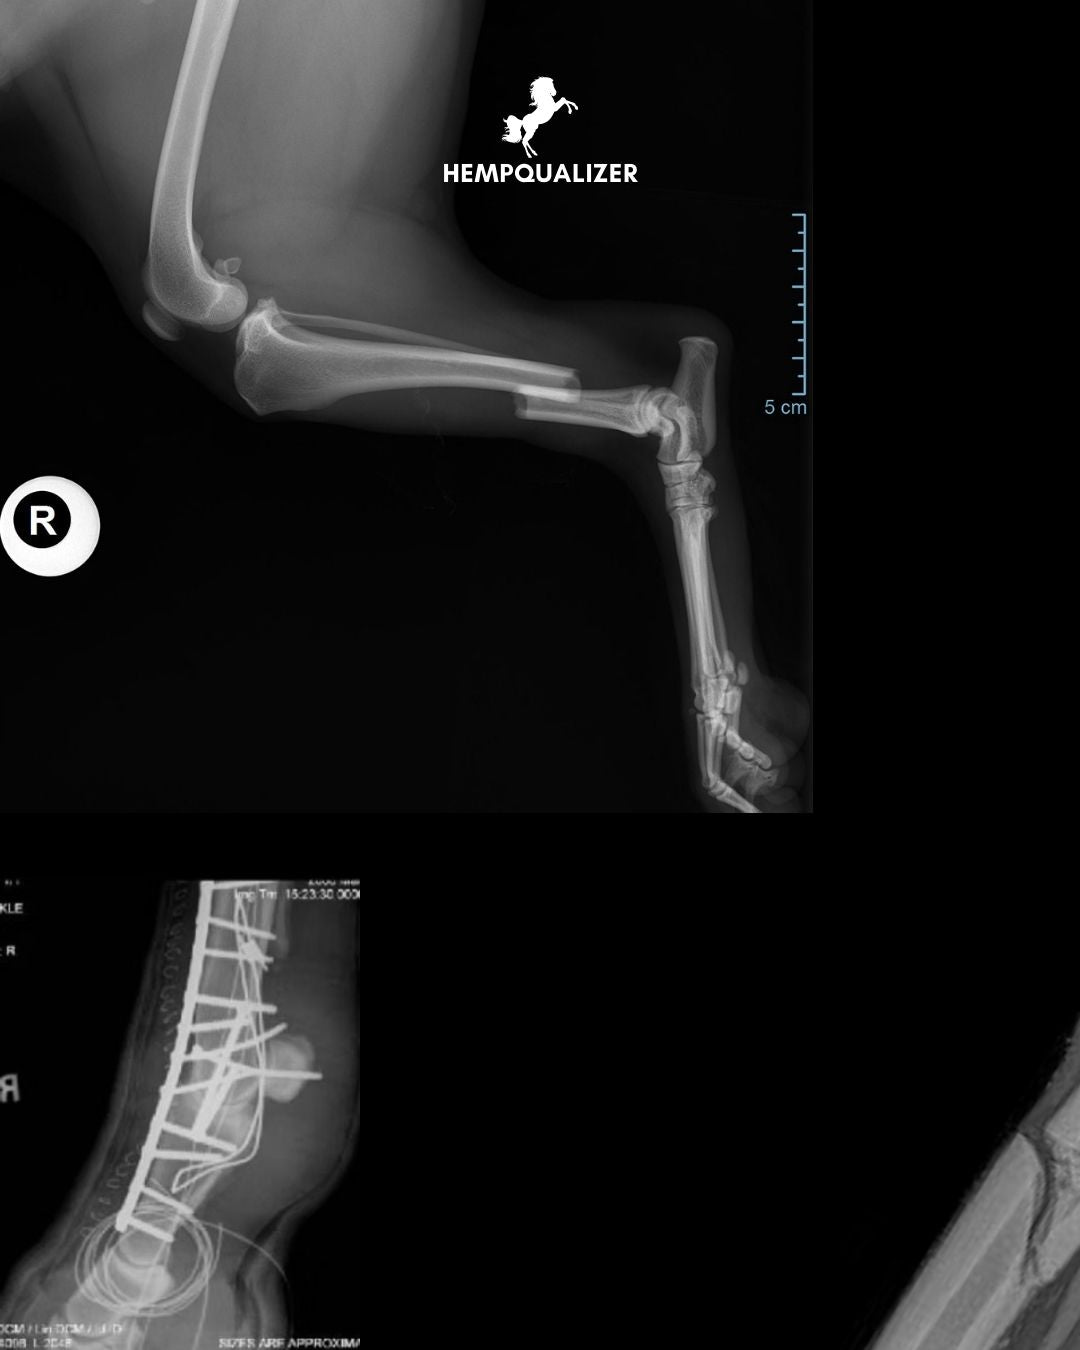

Why a Horse’s Broken Limb Is a Tragedy

Anatomy Leaves No Doubt

A broken leg in a horse isn’t just a serious injury – it’s one of the most difficult and heartbreaking situations a horse owner, veterinarian, and the horse itself can face. Why? The answer lies in the unique anatomy of the equine limbs. Though they appear strong, they are actually delicate and heavily burdened.

1. The Whole Body Weight on Thin Legs

An adult horse weighs between 500–600 kg, and all of that mass is supported by four slender legs. For example, the cannon bone (metacarpal/metatarsal) measures only about 2.5–3 cm in diameter. Trying to bear weight on a fractured limb often leads to severe tissue damage and complications.

2. No Muscles = No Protection

Below the carpal joint (front legs) and hock (hind legs), there are no muscles—only bones, tendons, and ligaments. This means the bones are unprotected and unstabilized. Fractures quickly become open wounds, greatly increasing the risk of infection.

3. Poor Blood Supply and Thin Tissue Coverage

The lower limb tissue is extremely thin. When a bone is damaged, the blood supply can be disrupted, leading to necrosis (sequestrum) that easily becomes infected. Under these conditions, healing is extremely difficult.

8. Repair? Extremely Challenging

The bones are thin, and the forces are immense. Screws and plates must withstand up to 150 kg of weight per leg, yet they often loosen, become infected, or fail due to fragment shifting. Successful treatment demands the highest level of surgical skill—and still, success is not guaranteed.

• Closed, simple fractures below the fetlock joint: over 70% of horses return to work.

• Open, comminuted fractures or fractures of long bones: only 12–25% survive, even with intensive treatment.